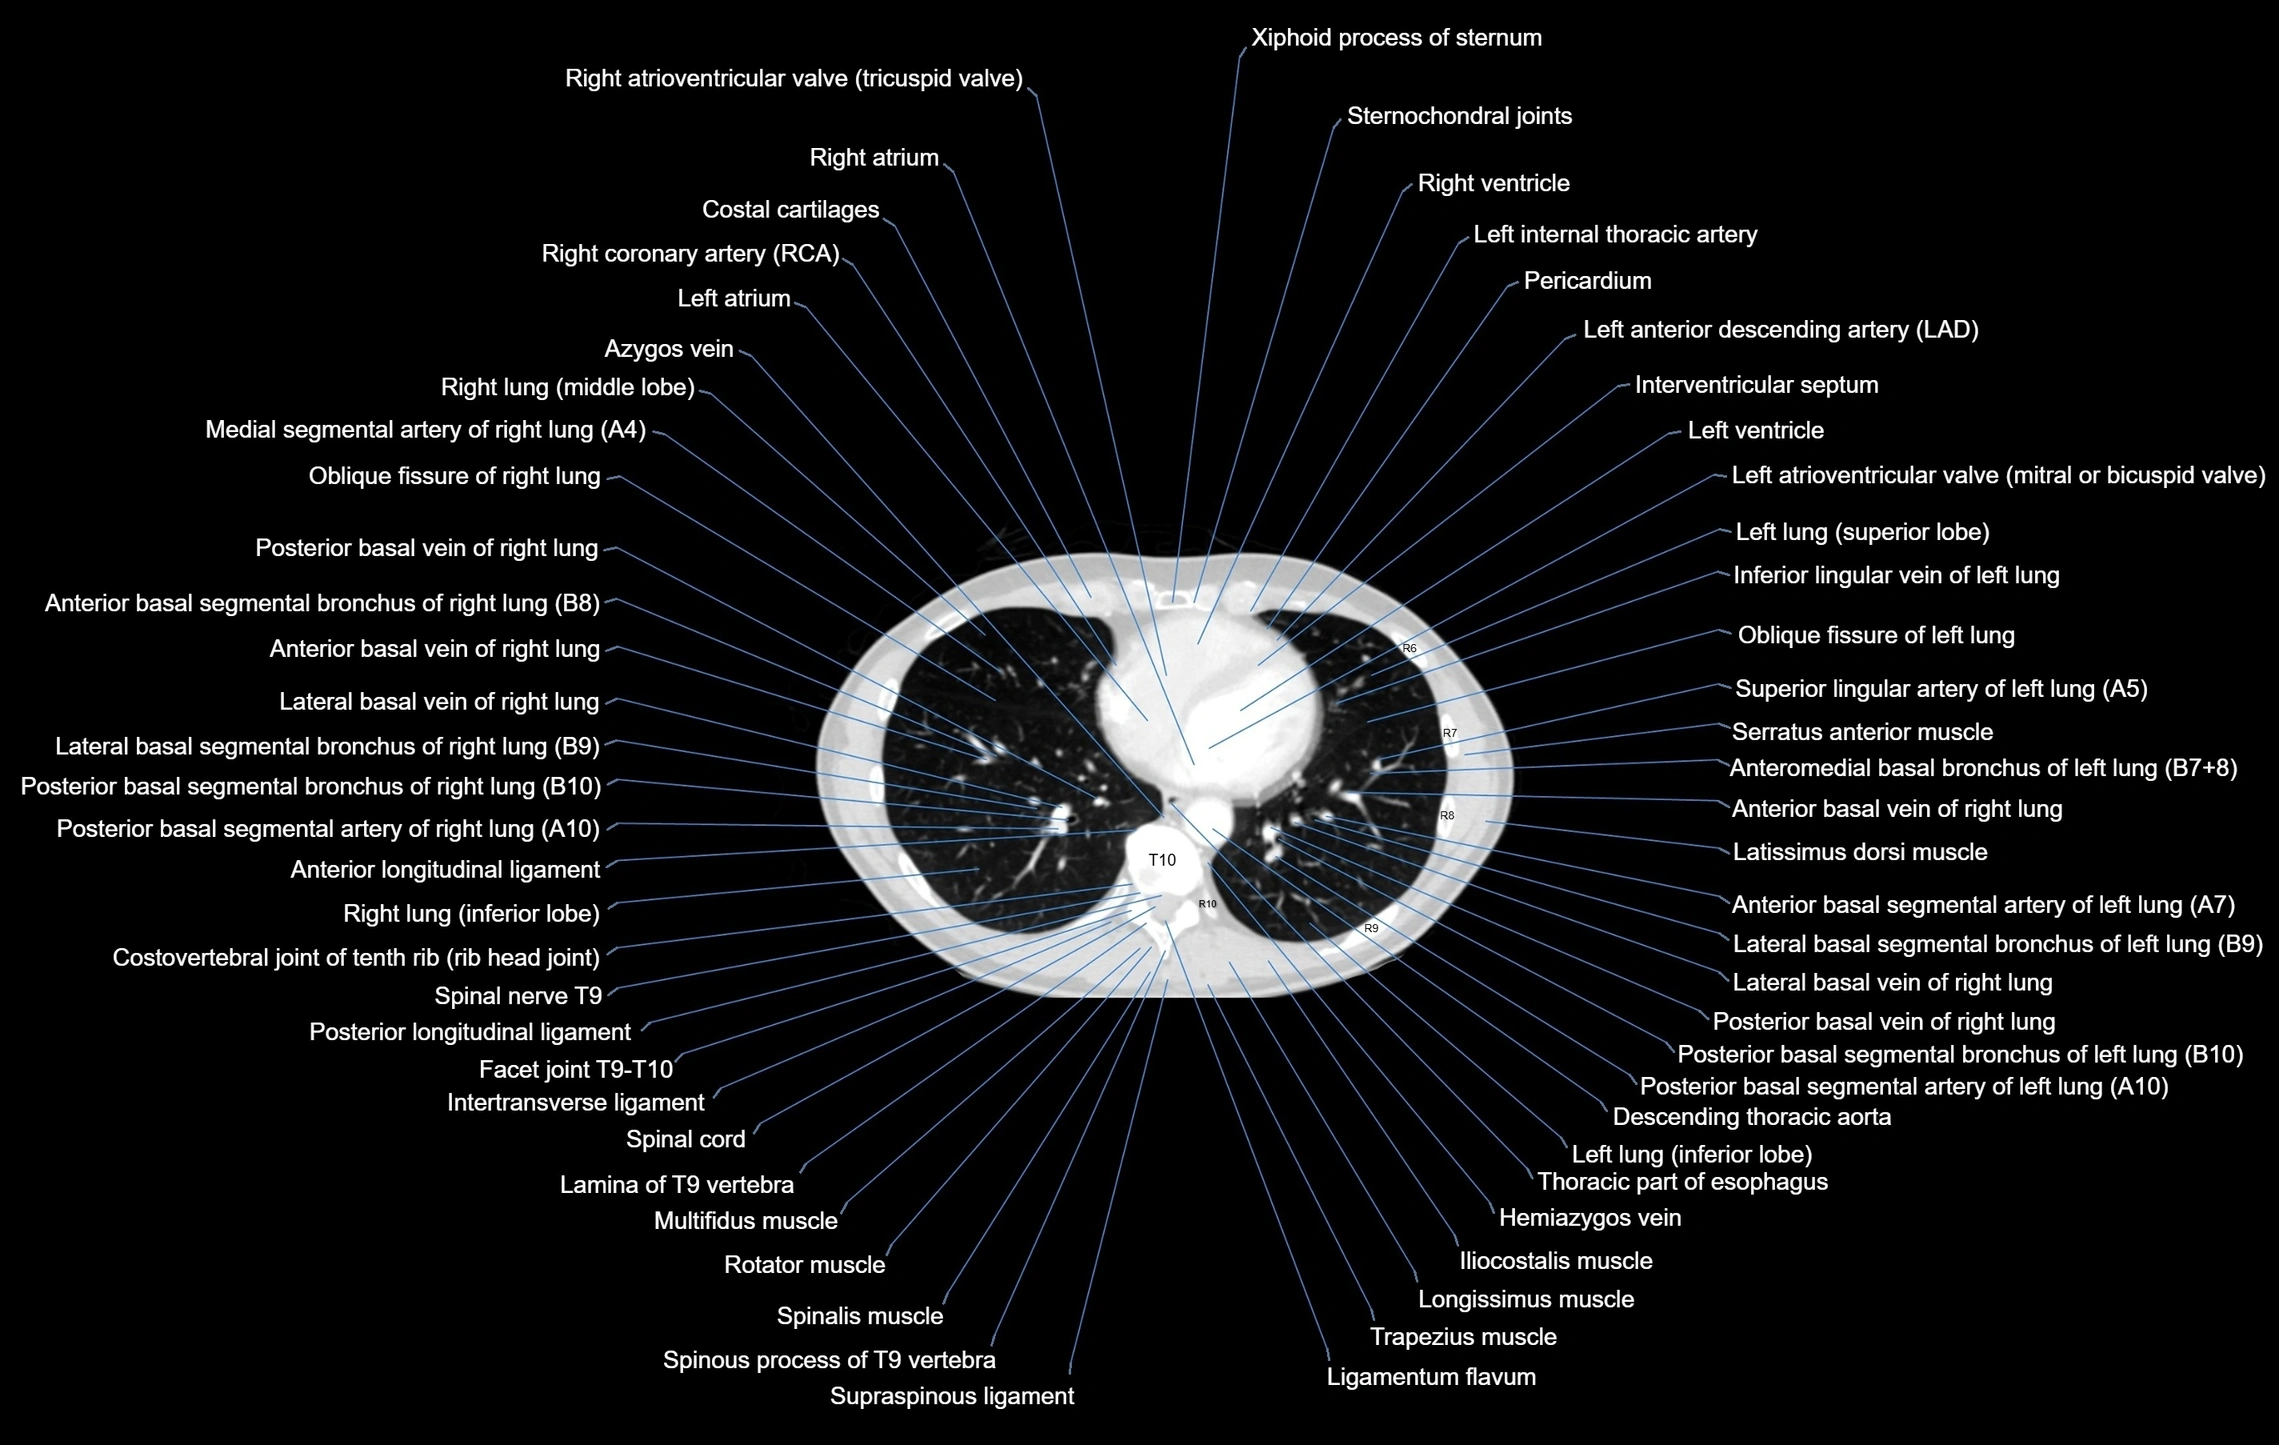

- Descending thoracic aorta

- Hemiazygos vein

- Interventricular Septum

- Left atrioventricular valve (mitral or bicuspid valve)

- Left atrium

- Left lung (inferior lobe)

- Left ventricle

- Middle lobe of right lung

- Multifidus muscles

- Posterior basal segmental artery of left lung

- Posterior basal segmental artery of right lung

- Posterior basal segmental bronchus of left lung (B10)

- Posterior basal segmental bronchus of right lung (B10)

- Posterior basal vein of left lung

- Posterior basal vein of right lung

- Right atrioventricular valve (tricuspid valve)

- Right atrium

- Right coronary artery (RCA)

- Right ventricle

- Thoracic part of esophagus